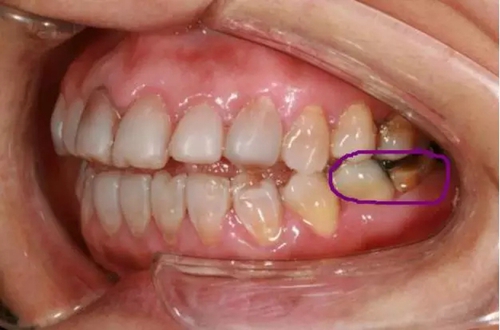

5,粉色線(xiàn)牙齒缺損(圖二)

美學(xué)修復(fù)不單是指擋擋門(mén)面,同時(shí)我們應(yīng)恢復(fù)患者正常的生理頜位及咬合關(guān)系,在滿(mǎn)足美觀的同時(shí)恢復(fù)患者的咀嚼功能。

(圖二)